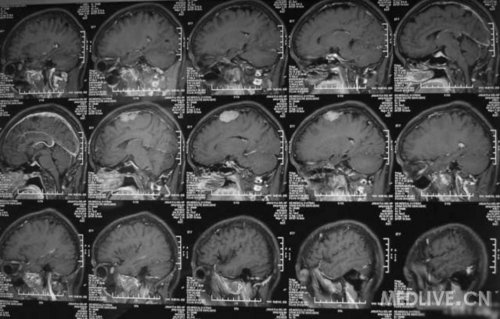

患者女,56岁,因右侧肢体活动不利2天于2011-06-15入院。查体:神志清,精神可,右侧肢体肌力4级,余无阳性体征。CT示左额叶占位,脑膜瘤可能性大。MRI示左额镰旁脑膜瘤,脑干左半亚急性梗塞。给予活血、神经营养、对症治疗,现一般情况好。请高手指点,何时手术切除脑膜瘤好啊?